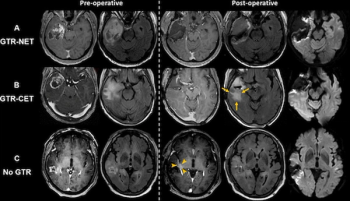

Irrespective of age or O6-methylguanine-DNA methyltransferase (MGMT) promoter methylation status, gross total resection of IDH wild-type glioblastomas was associated with a median overall survival of 32.6 months, according to new MRI research.

In a comparison of contrast-enhanced T1-weighted (CET1w) MRI (and T2-weighted MRI/FLAIR imaging, researchers found that only three out of 82 cases of glioma progression were solely detected with CET1w MRI.